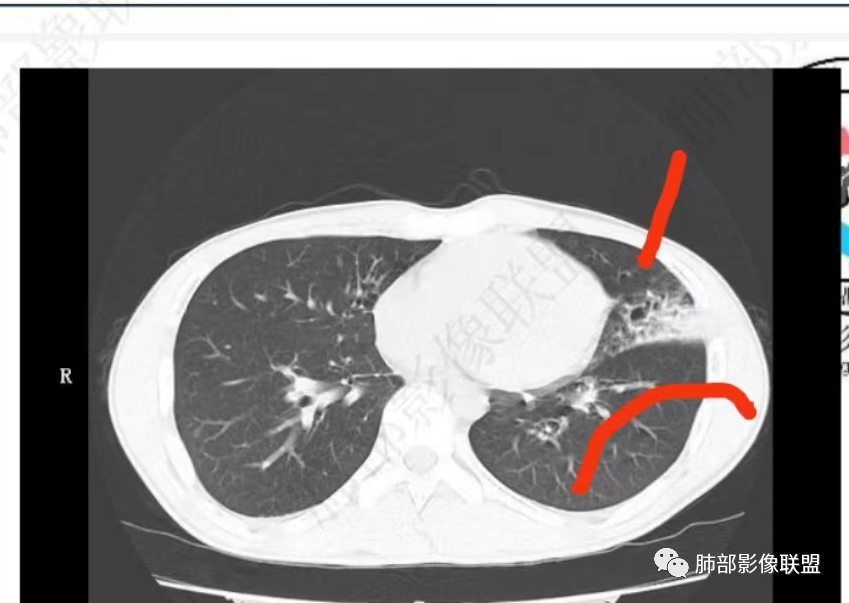

唐老师的经典名言:支扩背景的肺,判断病原体时一定要判断出支扩合并肉芽肿,或无肉芽肿性支扩。

实变边缘太模糊,渗出太明显了,不符合肉芽肿的特点

NTM支扩外一般无渗出性病变,而铜绿支扩外渗出常见

中叶内侧段的渗出病灶内支扩,支持铜绿,不支持NTM

你们再看这两个层面!支扩背景下出现肉芽肿病变。

2、影像特点:右肺中叶、左肺下舌段可见支扩。左肺下舌段及两肺下叶可见片状实变影及发结节影,病灶边界多显示不清,纵隔窗显示病灶密度较均匀,未见液化、空洞或钙化。左肺下叶部分病灶沿支气管分布,并可见局部支气管管壁增厚。